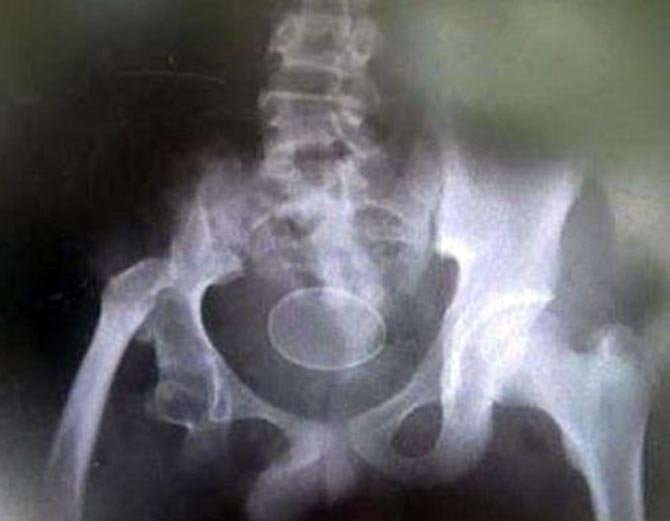

ਕੀਤੇ ਗਏ ਕਈ X - Ray

ਅਕਮਲ ਅਤੇ ਉਸਦਾ ਪਰਿਵਾਰ ਆਪਣੇ ਇਸ ਦਾਵਿਆਂ ਦੇ ਨਾਲ ਇਕ ਹਸਪਤਾਲ ਵੀ ਪੁੱਜੇ ਜਿਥੇ ਅਕਮਲ ਦਾ ਐਕਸ - ਰੇ ਵੀ ਕੀਤਾ ਗਿਆ, ਲੇਕਿਨ ਡਾਕਟਰਾਂ ਨੂੰ ਹੁਣ ਵੀ ਕੁੱਝ ਸਮਝ ਨਹੀਂ ਆ ਰਿਹਾ ਹੈ।